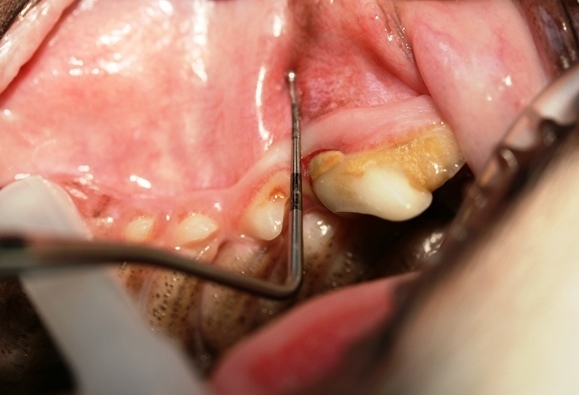

Der Chihuahua-Rüde ist sozusagen unser Zahnvorzeigepatient, und wir freuen uns jedes Jahr über seine topgepflegten Zähne, doch leider kam es anders als erwartet. Im Rahmen der gründlichen Untersuchung, die zu jeder Impfung dazugehören sollte, durfte uns Pico seine Zähne zeigen. Schnell fielen Rötung, Schwellung und Rückbildung des Zahnfleisches  im Bereich der vorderen Wurzel des Reißzahnes im linken Oberkiefer auf (Bild 1). Außerdem wies dieser Zahn im Vergleich zur Gegenseite eine deutliche Zahnsteinbildung auf. Die Parodontalsonde, ein spezielles Instrument mit einer Skalierung zum Ausmessen von Zahnfleischtaschen, brachte das Ausmaß des Schadens an das Licht. Die Sonde ließ sich fast einen Zentimeter tief in das Zahnfach einführen (Bild 2+3).

Was war geschehen? Trotz Zahnpflege hatte sich zwischen Zahnfleisch und Zahn eine Tasche gebildet, in die Bakterien eingedrungen waren. Die nachfolgende Entzündung hatte den Zahnhalteapparat erfasst und war jetzt bereits tief in das Zahnfach eingedrungen. Es war bereits zum Knochenabbau und zur Lockerung gekommen. Der Zahn war nicht mehr zu erhalten und musste leider entfernt werden.

In Picos Fall standen zunächst ein Kontrollbesuch beim Kardiologen zur Überprüfung seiner Herzmedikation sowie eine Blutuntersuchung an. Beides ergab keine Einschränkungen für den bevorstehenden Eingriff. Pico bekam eine für ihn maßgeschneiderte Narkose und wurde während der Operation kontinuierlich überwacht. Zunächst wurde ein Röntgenbild des betroffenen Zahnes angefertigt, um das Ausmaß der Entzündung und Lockerung einzuschätzen. Anschließend wurde das Zahnfleisch in Form eines trapezförmigen Lappen abgehoben und der darunter liegende Kieferknochen freigelegt. Der Zahn wurde entsprechend seiner drei Wurzeln mit einer Fräse in drei Segmente zerlegt. Während die vorderen beiden Wurzeln geschlossen entfernt werden konnten, wurde für die hintere intakte Wurzel der Kieferknochen eröffnet und die Wurzel nach Lockerung offen entnommen. Nach Glättung der Knochenkanten wurde die Wunde mit  dem zuvor präparierten Zahnfleischlappen mit selbstauflösendem Nahtmaterial verschlossen. Pico konnte bereits eine Stunde nach dem Eingriff auf seinen eigenen Beinchen Frauchen entgegenlaufen.